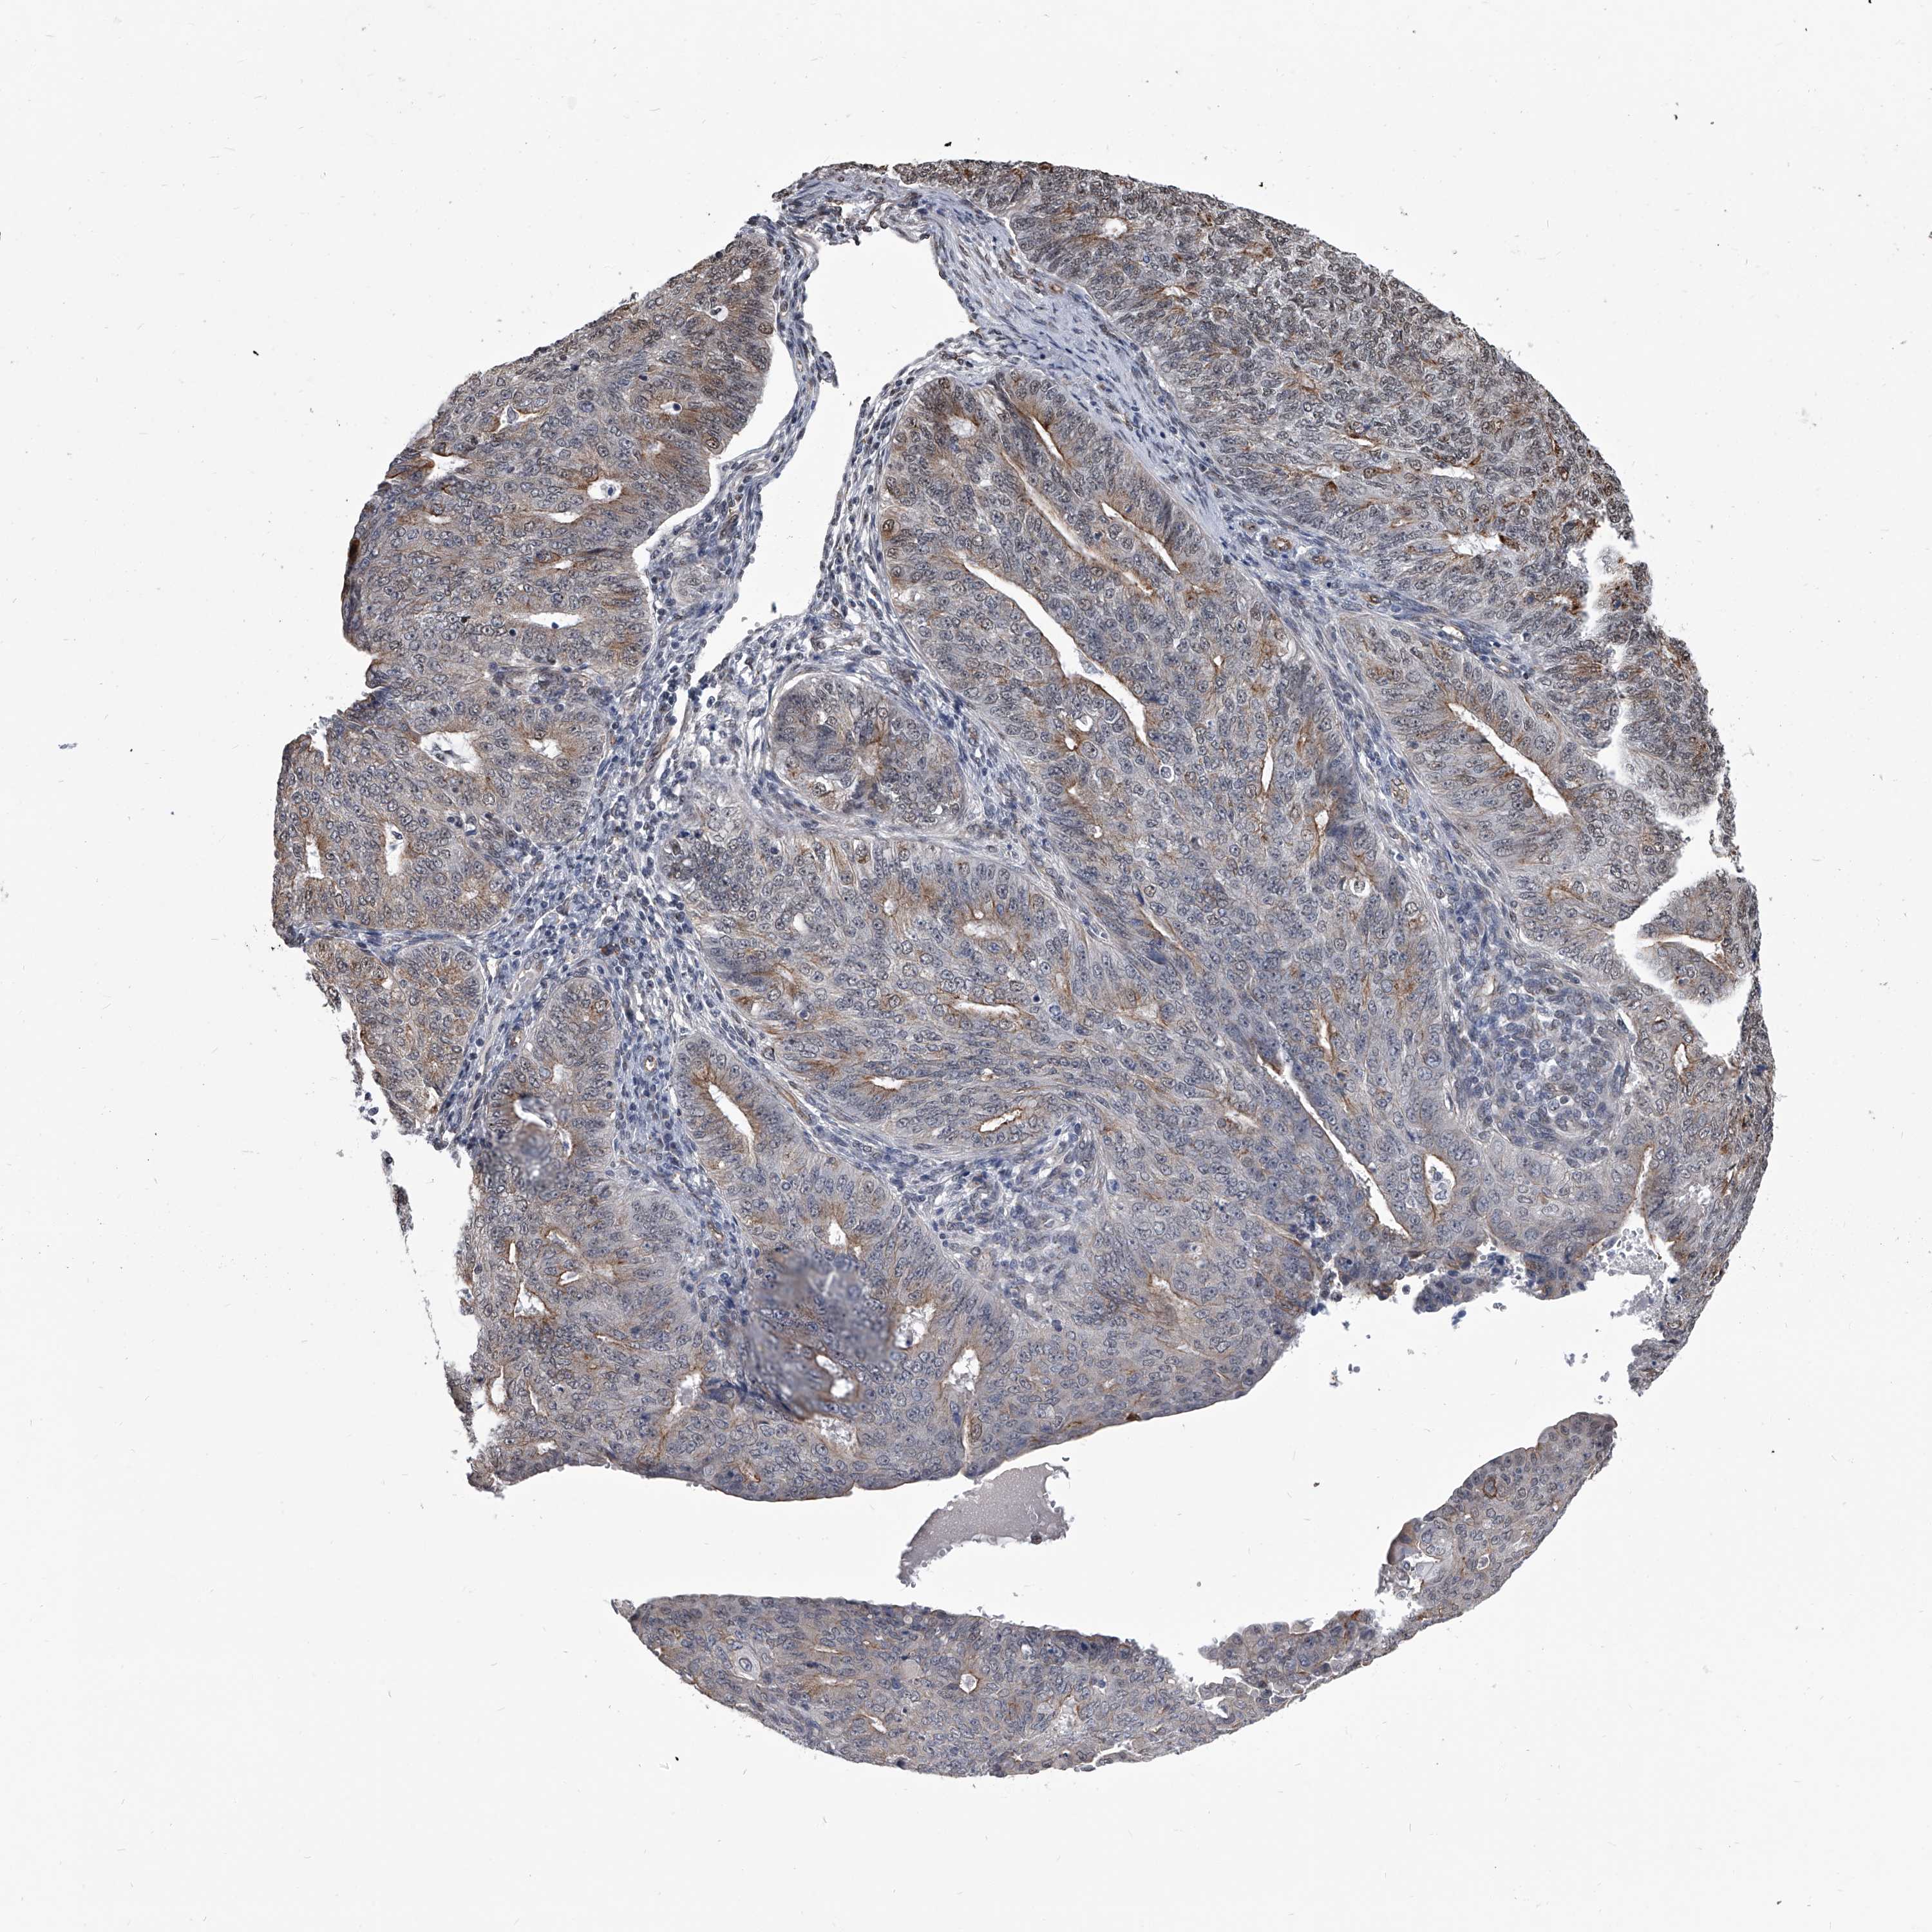

ENDOMETRIAL CANCER - Protein expressioni

A mouse-over function shows sample information and annotation data. Click on an image to view it in a full screen mode. Samples can be filtered based on level of antibody staining by selecting one or several of the following categories: high, medium, low and not detected. The assay and annotation is described here.

Note that samples used for immunohistochemistry by the Human Protein Atlas do not correspond to samples in the TCGA dataset.

Antibody stainingi

Antibody staining in the annotated cell types in the current human tissue is reported as not detected, low, medium, or high, based on conventional immunohistochemistry profiling in selected tissues. This score is based on the combination of the staining intensity and fraction of stained cells.

Each image is clickable and will lead to virtual microscopy that enables deeper exploration of all samples and also displays staining intensity scores, fraction scores and subcellular localization as well as patient and tissue information for each sample.

Antibody HPA030090

Antibody HPA030091

Staining

High

Medium

Low

Not detected

Intensity

Strong

Moderate

Weak

Negative

Quantity

>75%

75%-25%

<25%

None

Location

Nuclear

Cytoplasmic/membranous

Cytoplasmic/membranous,nuclear

Adenocarcinoma, NOS

Adenocarcinoma, metastatic, NOS